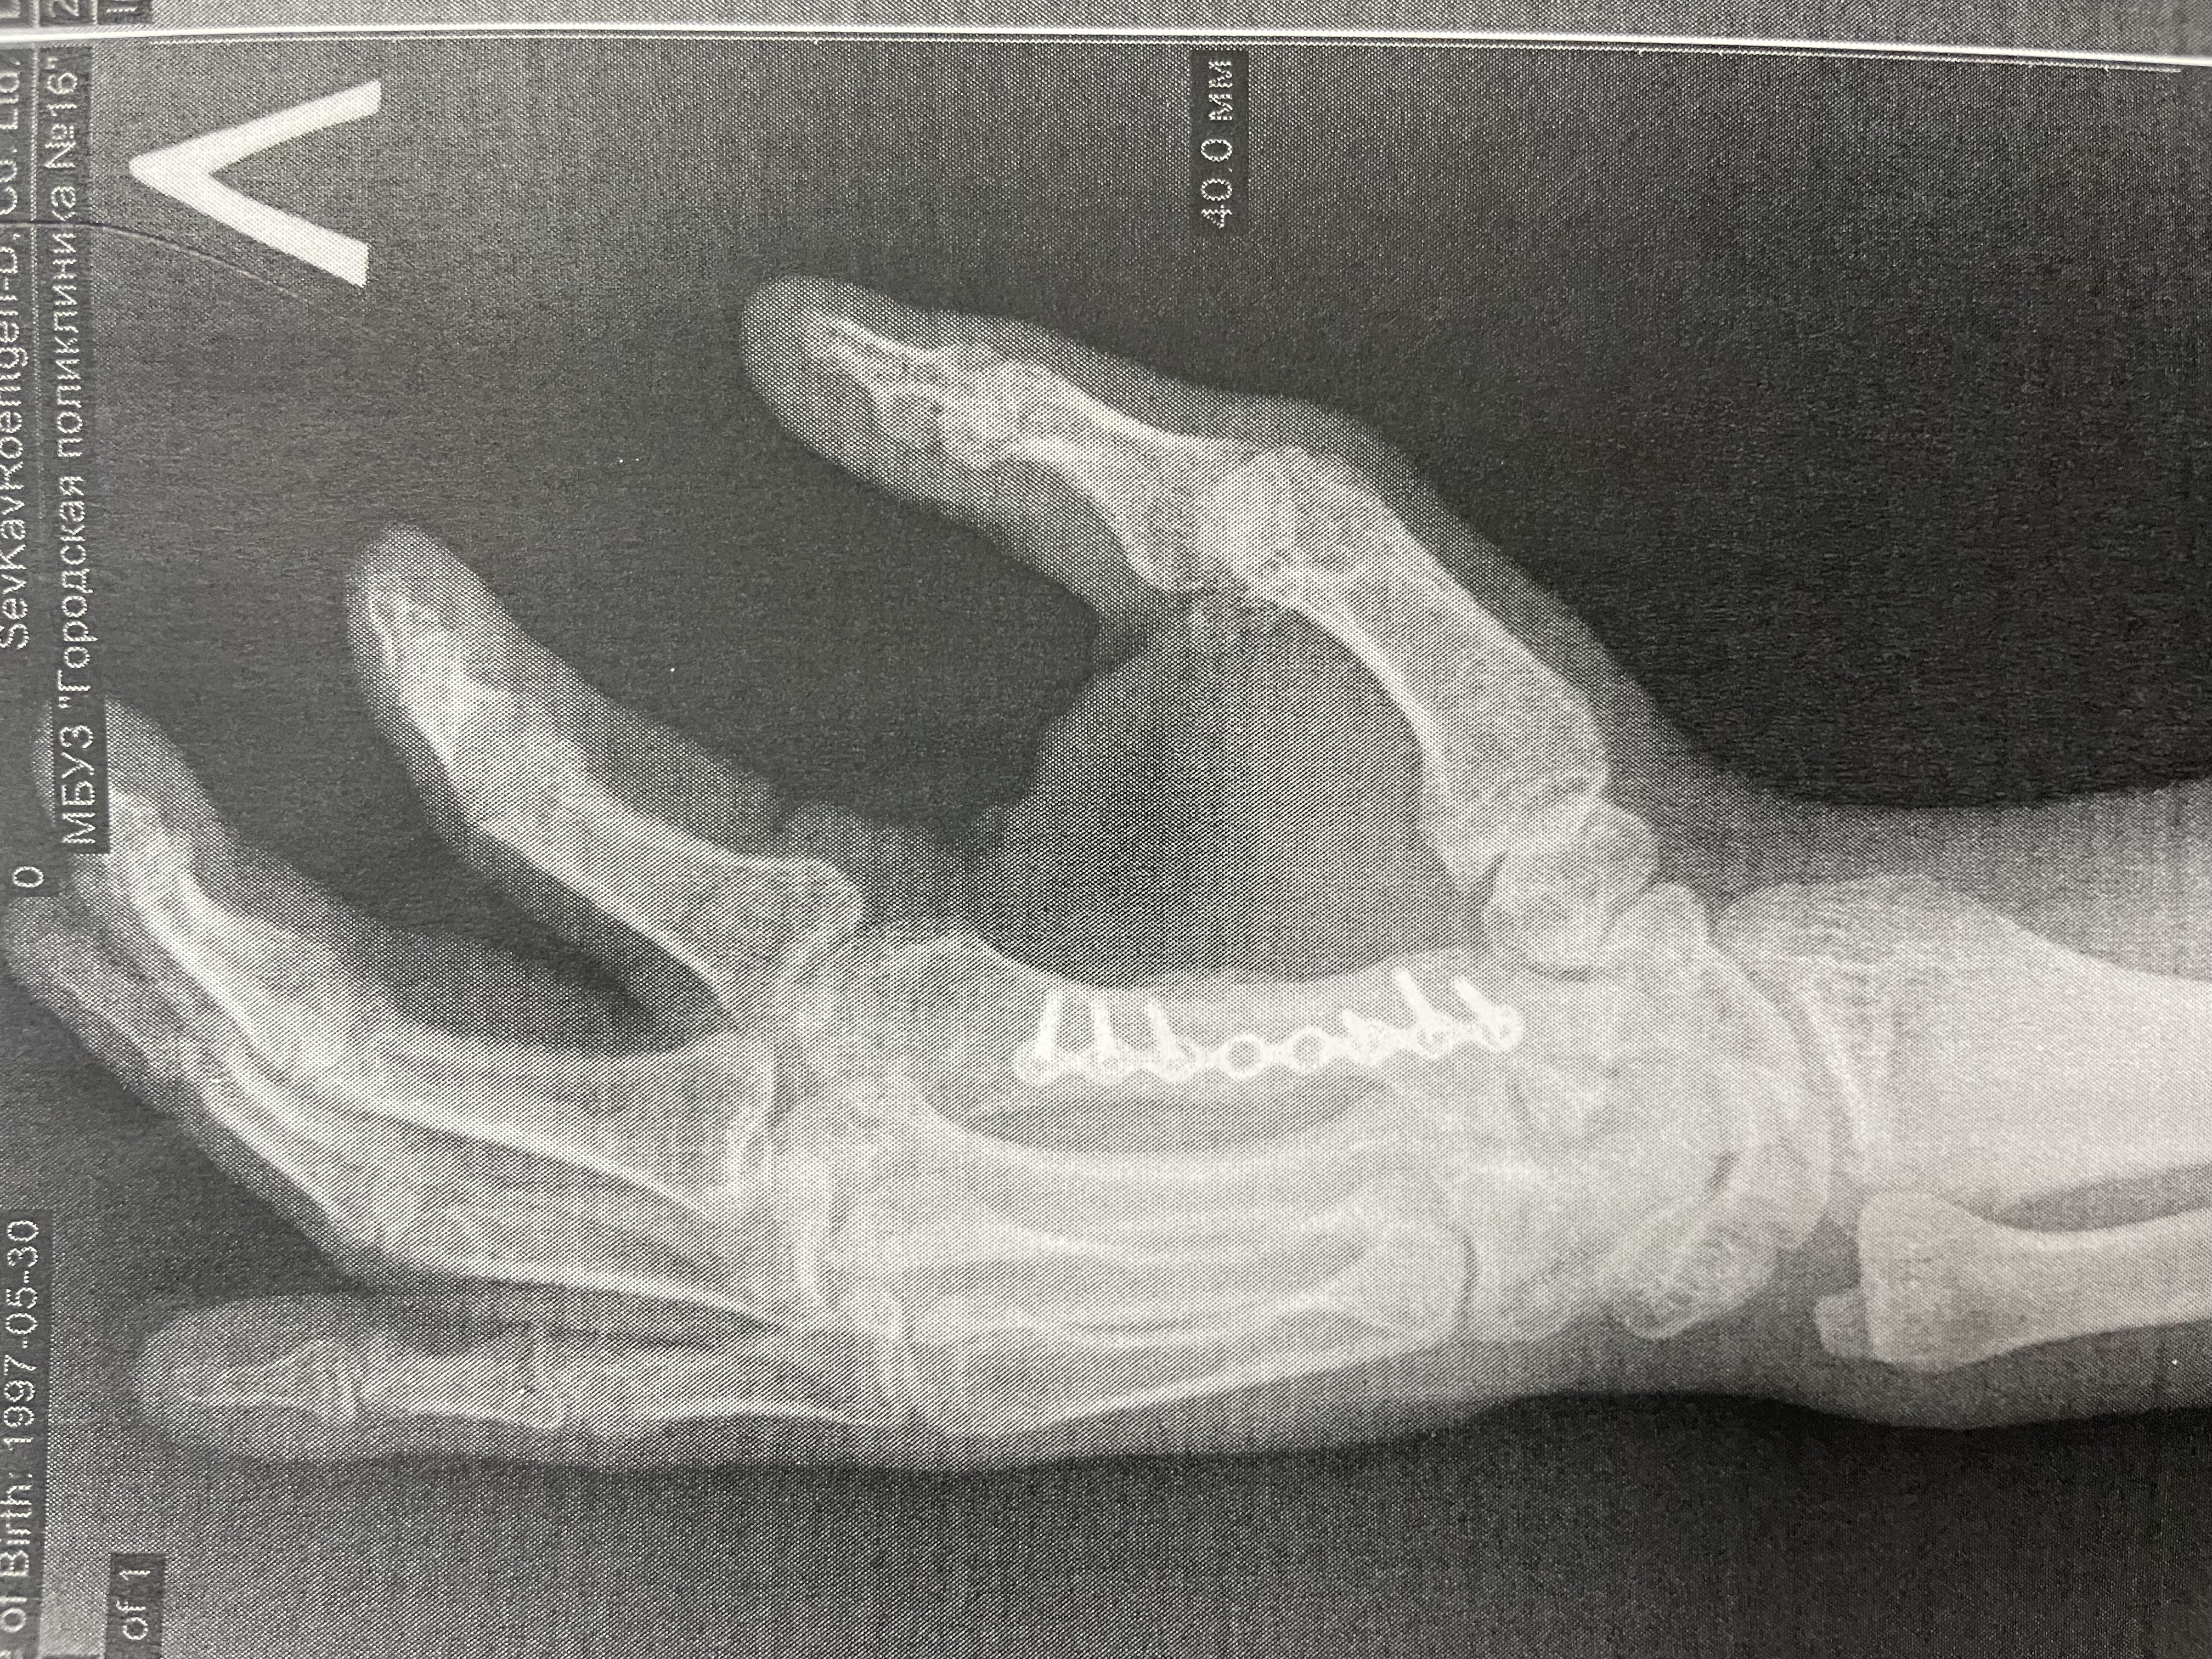

Переломы пястных костей диагностируются с клинического осмотра, во время которого врач оценивает симптомы и проводит физикальное обследование. Основным методом диагностики является рентгенография, которая позволяет визуализировать состояние костей и выявить наличие перелома. В некоторых случаях может потребоваться компьютерная томография (КТ) для более детального изучения повреждений, особенно если есть подозрение на сложные или нестандартные переломы.

Пациент с переломом 5 пястной кости по типу «боксёрского» удара. На фото и видео — деформация и ограничение функции до вмешательства.

Клинический случай: остеосинтез перелома 2 пястной кости — до операции

Пациент с нестабильным переломом 2 пястной кости. Документируем боль, отёк и ограничения движений перед оперативным лечением.